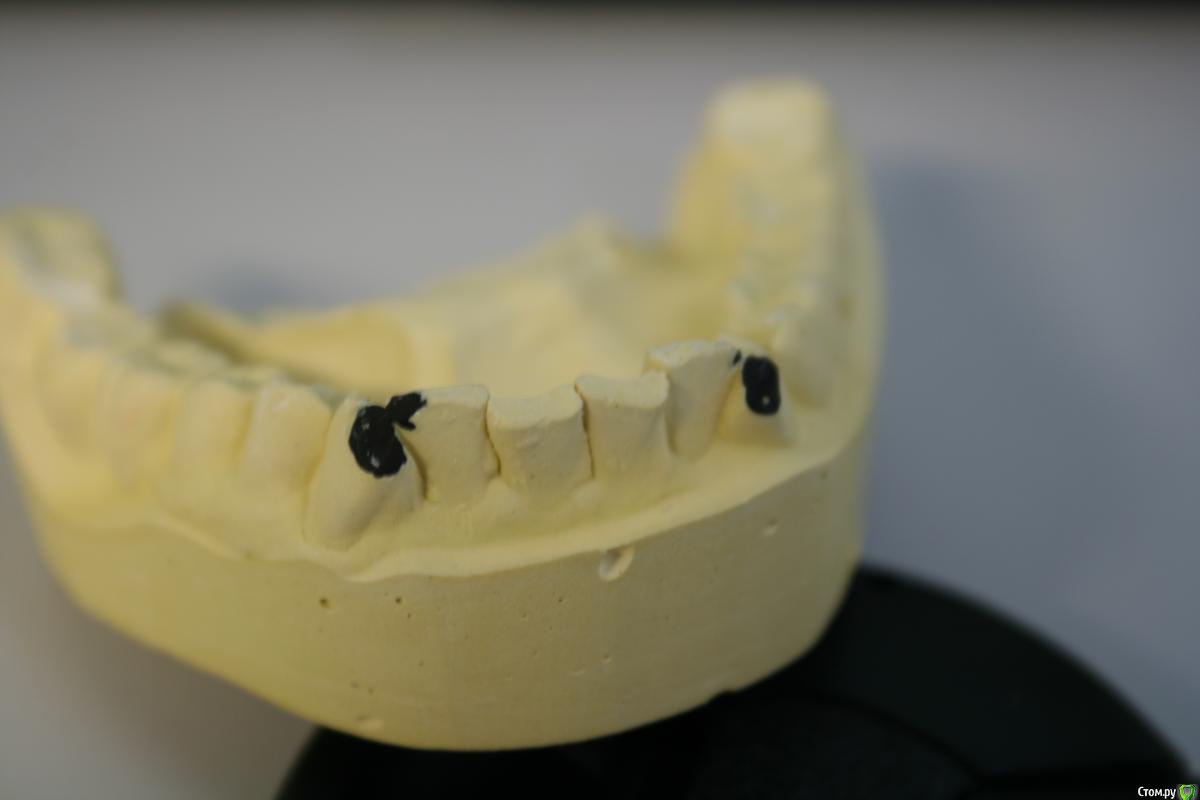

kramer Опубликовано 21 января, 2018 Автор Поделиться Опубликовано 21 января, 2018 Но даже в случае тотала, непонятно, что делать с 43 и 33 из-за их положения. Ссылка на комментарий

chervoncevdaniil Опубликовано 21 января, 2018 Поделиться Опубликовано 21 января, 2018 Но даже в случае тотала, непонятно, что делать с 43 и 33 из-за их положения.Мне кажется за счет коронок их выровнять нереально Ссылка на комментарий

kramer Опубликовано 21 января, 2018 Автор Поделиться Опубликовано 21 января, 2018 (изменено) Мне кажется за счет коронок их выровнять нереальноПридётся оставить как есть, для "естественности", по крайней мере не придётся отпиливать им углы в случае повышения прикуса. Либо ортодонтия Изменено 21 января, 2018 пользователем kramer Ссылка на комментарий

art700 Опубликовано 21 января, 2018 Поделиться Опубликовано 21 января, 2018 Без ортодонтии красиво не будет) Ссылка на комментарий

kramer Опубликовано 23 января, 2018 Автор Поделиться Опубликовано 23 января, 2018 В целом,я думаю нормально,но чем продиктована длина зубов? Если хотите увеличить длину,ведь ее можно увеличить за счет небольшой коррекции десневого края,а не за счет удлинения зубов.Опять же не понятна линия улыбки пациента. И не совсем понятна линия горизонта. Попробуйте сделать мокап в орту и посмотреть,что получится.Я не могу сделать такой мокап без спиливания клыков. Дело не только в длине, а ещё в развернутых двойках. Если их выравнивать коронками, не хватает места. Либо я че то не понимаю Ссылка на комментарий

kramer Опубликовано 23 января, 2018 Автор Поделиться Опубликовано 23 января, 2018 Это же ненормально - спиливать интактные зубы для подгонки протеза?) Ссылка на комментарий